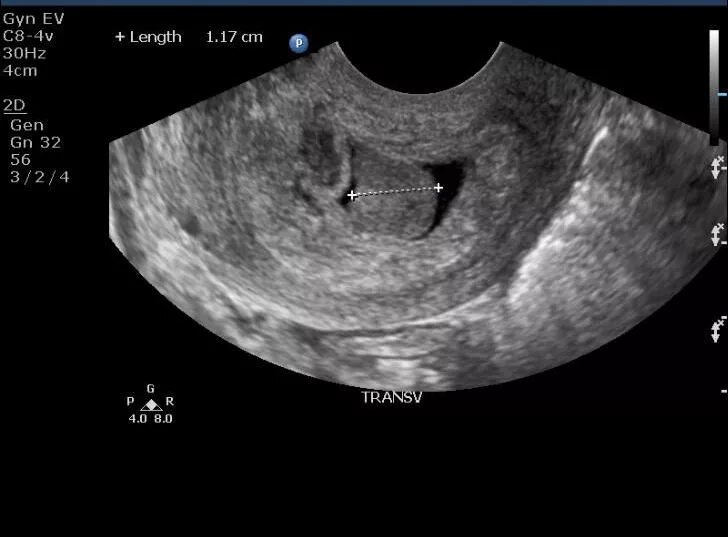

Полипы в матке что это такое